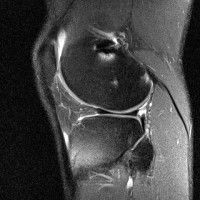

무릎 mri 간단히 봐주실 수 있으시나요 ㅠㅠ

안녕하세요 8년전 십자인대 수술하고 최근 무리한 운동에 무릎 불편감이 생겨서

mri 찍었습니다.

진단결과는 첫 찍은 병원에서 활액막염 이라는 진단을 받았습니다. 혹시 봐주실 수 있으실까요?

• 1번 째 사진

• 안녕하세요. 강성주 의사입니다.

올라온 MRI가 단편적이라서 정확한 진단에 어려움이 있지만 십자인대에는 큰 이상이 있지는 않은것 같으며, 무릎관절내 물이 있는 것으로 보아 활액막염의 진단이 맞을 것 같습니다.

하지만 단편적인 영상이기 때문에 촬영병원에서 정확한 판독지 등을 받으시는 것이 좋겠습니다.